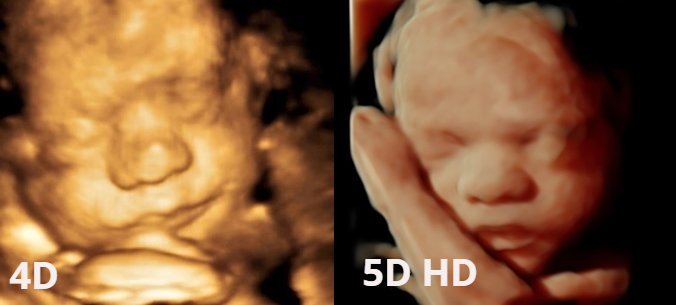

Imagen 8K ¿Qué es?                                                                                                        La imagen 8K es una técnica novedosa que aporta mayor sensación de realismo a las imágenes que se obtienen mediante la adquisición de ecografía 5D que, ya de por sí, resulta ser una técnica ecográfica hiper-realista.                                 Dicha técnica suaviza y texturiza las imágenes obtenidas, aumenta los contrastes y se incorporan detalles que aumentan, si cabe, la sensación de realismo. A petición del cliente la imagen seleccionada es procesada y entregada durante los días posteriores a la realización de la ecografía 5D.                                 En Centre Miramed estamos orgullosos de poder poner a disposición de nuestros/as clientes/as la técnica 8K como ejemplo de vanguardia y crecimiento continuado.